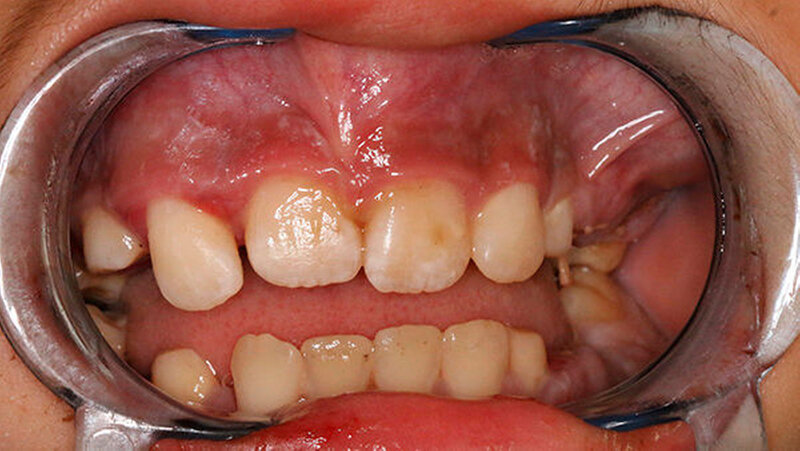

Die Anamnese war aufgrund der Sprachbarriere erschwert, es hieß seitens der Eltern, der Zustand bestünde schon seit einigen Tagen. Es wurden keine Vorerkrankungen und keine feste Medikation angegeben. Die klinische Untersuchung zeigte eine weiche, wenig schmerzhafte Schwellung im linken Oberkiefervestibulum (Abbildung 1).

Die Zähne 64, 65 und 75 waren kariös zerstört. Weiterhin wurden bei der eingehenden Untersuchung zweit- bis drittgradige Lockerungen an sämtlichen Milchmolaren des Oberkiefers, zweitgradige Lockerungen der Milchmolaren im Unterkiefer sowie erst- bis zweitgradige Lockerungen der bleibenden Inzisivi am Oberkiefer festgestellt.

Die Mundschleimhaut war intakt, die Sensibilität im Gesichtsbereich und die Mundöffnung mit 33 mm Schneidkantendistanz waren unauffällig. Zervikal konnten beidseits mehrere vergrößerte Lymphknoten palpiert werden, die übrige körperliche Untersuchung zeigte keine Auffälligkeiten. Die laborchemischen Entzündungsparameter (Leukozyten, CRP) waren im Normbereich.